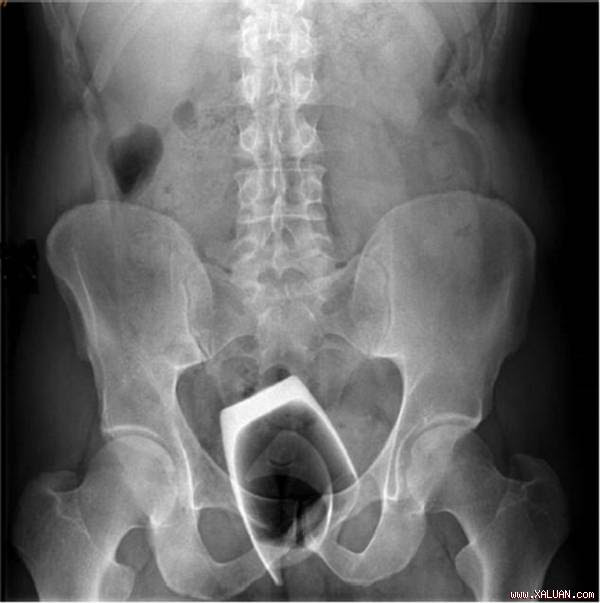

Phim chụp X-quang của bệnh nhân. Anh: BMJ.

Ông không cảm thấy đau đớn song 2 ngày sau phải đến bác sĩ để được tư vấn vì cảm thấy lo lắng về sức khỏe. Kết quả chụp X-quang cho thấy các mảnh thủy tinh trong trực tràng bệnh nhân. Các bác sĩ phải mổ mở rộng trực tràng bệnh nhân để đưa thiết bị vào kiểm tra. Các mảnh vỡ sau đó đã được lấy ra.